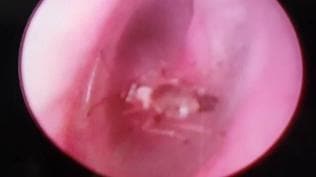

Doktorlar da şaşkına döndü: Kulağından çıktı!